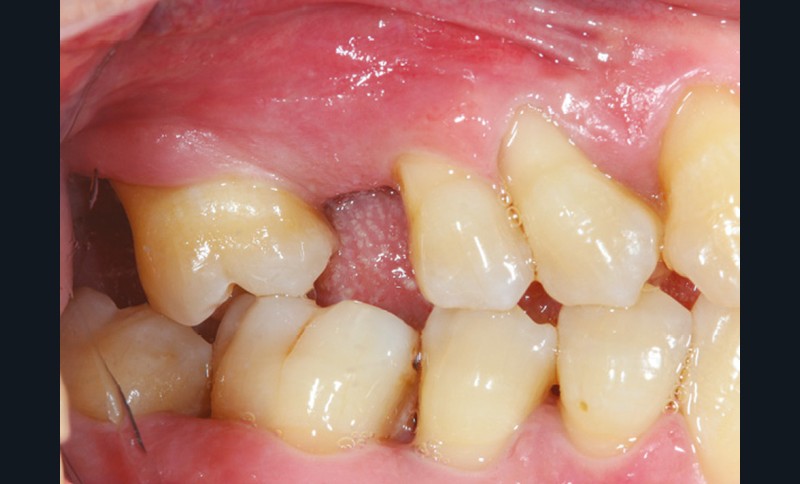

La perte d’une ou plusieurs dents entraîne la perte des points de contact, responsables de la stabilité et de la continuité de l’arcade. Par conséquent, une avulsion a pour première conséquence la migration ou la version d’une ou plusieurs dents distales (fig. 1 et 2). Cela est vrai en antérieur comme en postérieur.

L’âge de survenue de l’extraction semble avoir une importance sur l’apparition des migrations et des versions : si l’édentement intervient après 26 ans, les conséquences sont moins fréquentes [9].